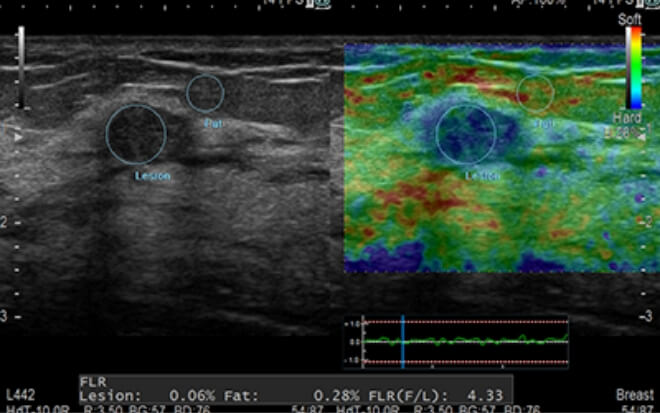

超音波(経膣)・ABUS(乳房自動超音波)

ABUS(乳房自動超音波)・マンモグラフィ